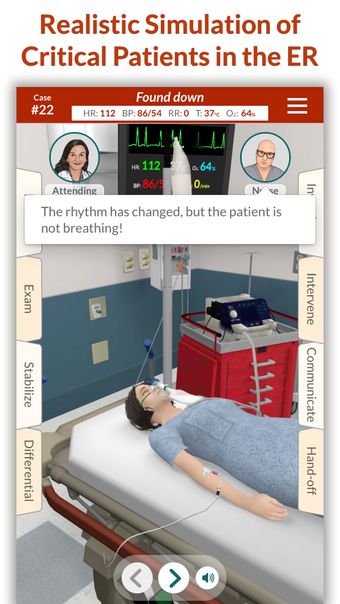

Full Code - Emergency Medicine Simulation è un'applicazione Android sviluppata da Minerva Medical Simulation Inc. È una versione completa con licenza di un'applicazione di stile di vita che rientra nella sottocategoria medica. È un'applicazione di simulazione intuitiva, mobile-first che offre oltre 160 casi virtuali realistici e un'interfaccia coinvolgente simile a un gioco, preferita dai professionisti medici di tutto il mondo. L'applicazione è progettata per aiutare gli studenti e i professionisti medici a acquisire fiducia nel trattamento di casi complessi e offre 0,5 crediti AMA PRA Categoria 1™ per ogni caso Full Code giocato con Full Code Pro+CME.

L'applicazione consente agli utenti di esercitarsi in diagnosi cliniche rare e rischiose in un ambiente sicuro in modo da poter affrontare casi complessi del mondo reale con fiducia. Con oltre 160 casi in 31 specialità, Full Code consente di esercitarsi in simulazioni mediche on-demand ogni volta che si ha una pausa, ovunque ci si trovi. L'applicazione è ottimizzata per la portabilità e l'accessibilità ed è disponibile su qualsiasi dispositivo mobile, desktop o tablet. Full Code è accreditato attraverso l'ACCME e, con la sua sottoscrizione PRO+CME, gli utenti possono completare i loro requisiti di formazione medica continua (CME) con sfide di simulazione flessibili e piacevoli. È un'applicazione eccellente per i professionisti medici che vogliono migliorare le proprie competenze e acquisire fiducia nel gestire casi complessi.